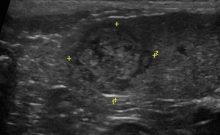

こんなときに、威力を発揮するのが超音波検査(エコー)です。※ 当院では定期的な健康診断として、画像診断(レントゲンや超音波検査)を組み入れた健診をオススメしています。

現在では超音波診断技術の進歩で画像所見から、ある程度の予想はたてられますが、肉眼で術前に良性or悪性を完全区別することはほぼ不可能です。

脾臓内におさまっている病変については、数ヶ月ごとに超音波検査にてモニターしていきますが、脾臓表面から盛り上がってきている病変の場合には摘出手術をオススメしています。脾臓原発性腫瘍の術前診断は難しいというのが、現状だからです。

超音波診断のとおり、脾臓表面から膨隆していました。病理結果は悪性腫瘍ではありませんでしたが、放置すると、リンパ組織がさらに融合してより大きな腫瘤を生じ脾臓破裂(突然死)を起こすというコメントを病理診断医よりいただきました。(脾臓摘出したあと、割面をいれたものです。エコー画像と一致した部位に病変があります)